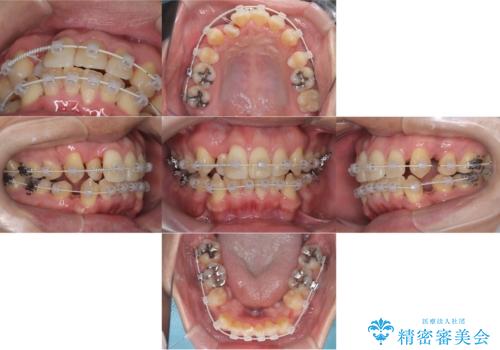

- 矯正装置

- ワイヤー(審美装置)

- 2年2ヶ月

デコボコの量が多かったため上下左右4を抜歯してワイヤー矯正で治療を行いました。

正面から見たときに右上2が全く見えないくらい、右上2が後ろに引っ込んでいる状態でしたが綺麗に並べる事が出来ました。

笑った時のスマイルラインもかなり綺麗になり大変ご満足いただく事が出来ました。

スムーズに治療を進める事ができ、2年2か月で治療をお終えました。

顔貌に対して歯の正中も合いました。